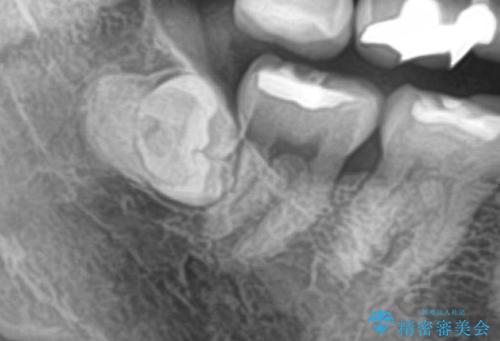

- 親知らずを抜歯したいとの事で来院。

パノラマ,CT撮影を行い安全なことを確認して抜歯を行いました。

抜歯後1週間後に抜糸と消毒を行い処置は完了になります。